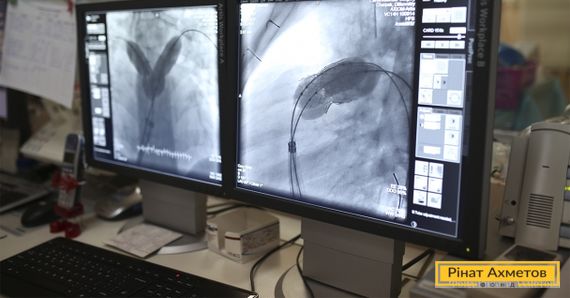

Эндоваскулярный метод означает, что операция проводится без разреза грудной клетки. Но для этого нужен окклюдер. Он представляет собой спираль размером шесть миллиметров. Через небольшой разрез на бедре и артерию окклюдер с потоком крови проникает в проблемное место прямо в сердце. Раскрываясь подобно зонтику, имплант закрывает проток и со временем зарастает мышечной тканью.